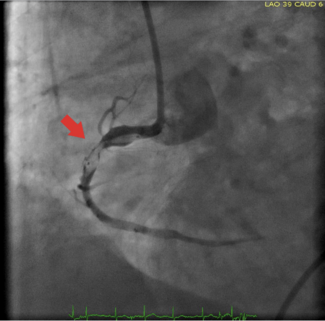

These images illustrate an attempt to pull back the balloon of an implanted proximal stent swiftly (before it was completely deflated) just following unplanned disengagement of the guiding catheter from the right coronary ostium.